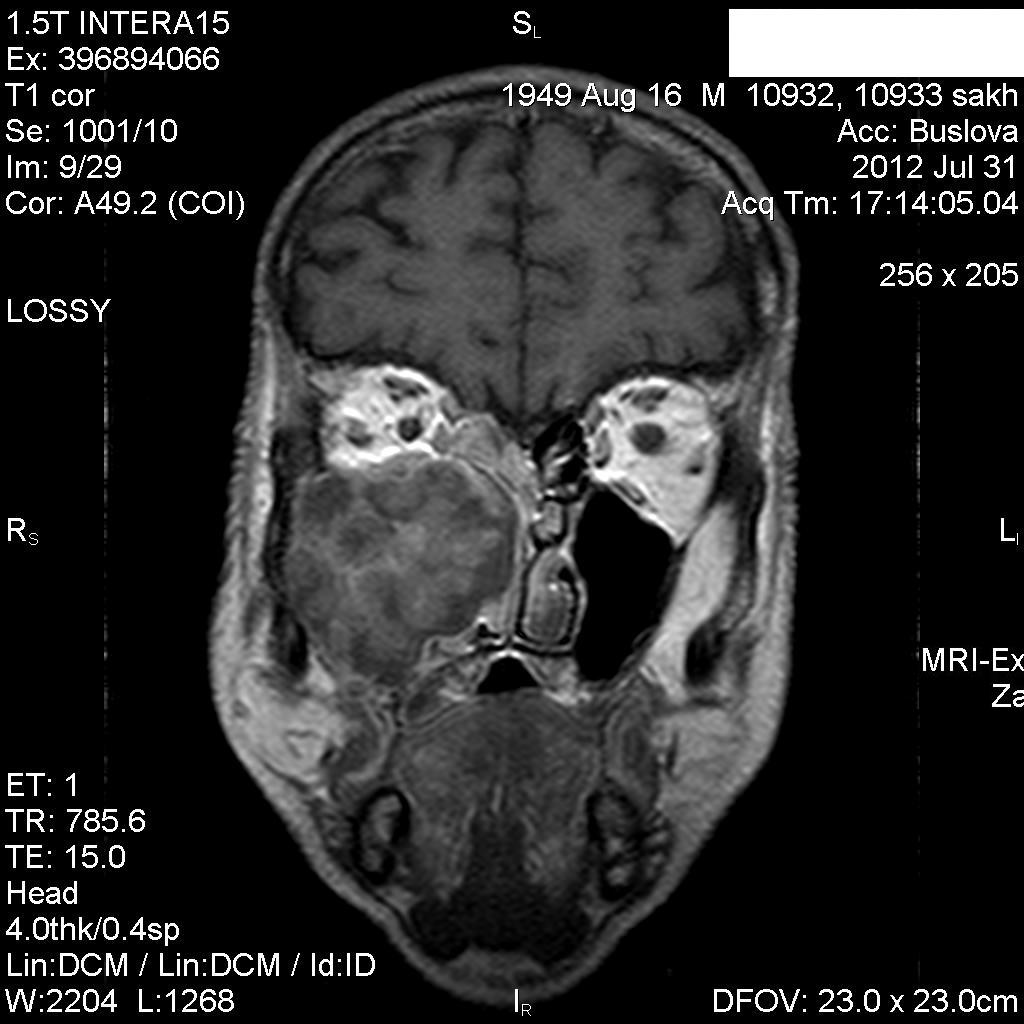

Мужчина лечился около месяца от правостороннего гайморита.Неоднократно пунктировали.Выписался из стационара, через 3 дня попал к другому ЛОР-врачу, который направил пациента на КТ, но волею судеб он оказался у нас.Визуально: незначительный экзофтальм справа, отек скуловой области, который периодически исчезает.Пыталась добыть его рентгеновский снимок пазух через знакомого отоларинголога, вхожего в лечебное учреждение, где лечился пациент-бесперспективно ( просто исчез, со слов лечащего врача-обычный правосторонний гайморит), хотя просила всего-то для себя, чтобы самой в такую ситуацию не попасть.

В заключение выставила объем.

постконтраст

Где-то в душе грелась мысль о нагноившейся гематоме, пока не показала исследование нашему отоларингологу, который пытался помочь в поиске рентгенограммы.

Нашла похожее образование в книге Г.Труфанова как плоскоклеточный рак.

Вот буквально две недели назад у нас был почти аналогичный пациент , он тоже длительно ходил по врачам и лечился прогреваниями от стреляющих в висок болей. Пришел на МРТ случайно -отправила к ЛОР и челюстно-лицевым хирургам. Думаю и здесь есть озлокачествление хронического процесса. Трудно сказать есть ли деструкция медиальной стенки пазухи , деформация точно есть.